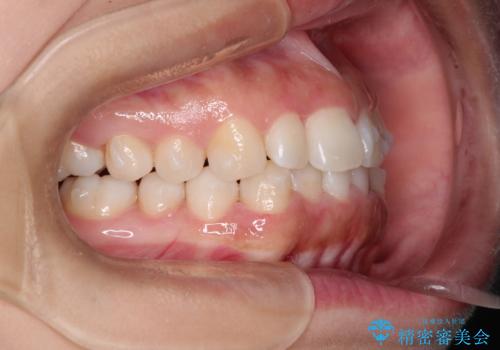

- 初診時には前歯部に捻転や叢生、臼歯部にも一部叢生が見られる状態でした。

インビザラインでの治療を計画し、行っていきました。

インビザライン治療により、捻転を含む歯列もしっかりと改善しています。

基本的な不正咬合部分は初回の30枚のマウスピースでほぼ改善しており、リファインメントでは前歯部の細かな調整など、患者様の要望を取り入れる形でシミュレーションをセットアップし、満足の行く結果に仕上がりました。